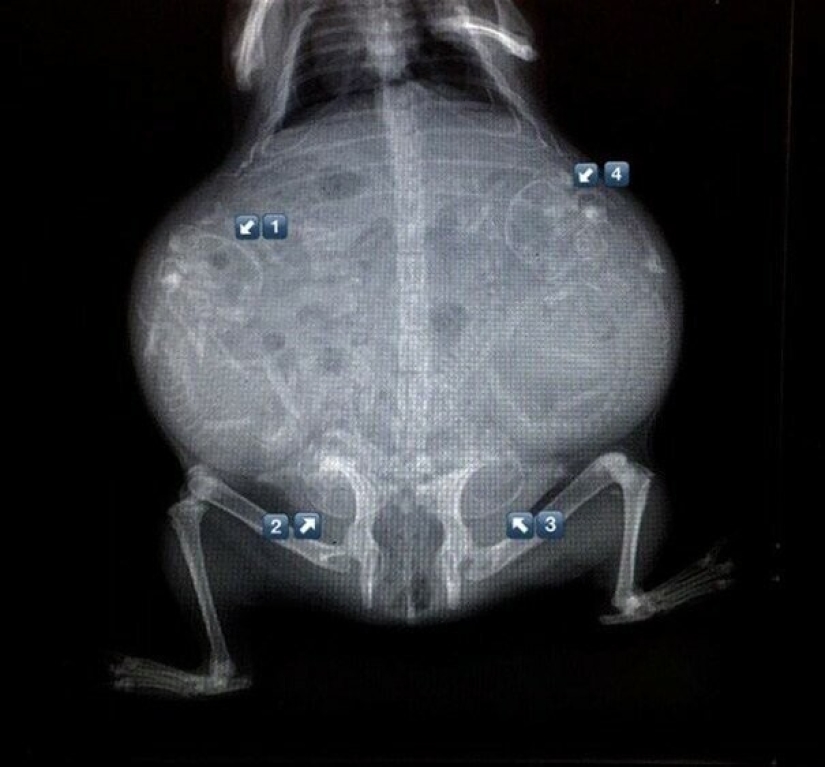

Quién vive en la casita: radiografías de animales preñados

Por Pictolic https://pictolic.com/es/article/quien-vive-en-la-casita-radiografas-de-animales-prenados.html¿Alguna vez te has preguntado qué sucede en el útero de una gata o una perra preñada? ¿Cómo encajan todos estos pequeños bebés allí y logran desarrollarse durante todo el embarazo? La mayoría de los animales preñados se examinan mediante rayos X. Y éstas, cabe señalar, son fotografías muy interesantes.

Especialistas que como parte de su trabajo observan animales que están listos para parir, compartieron estas sorprendentes imágenes de rayos X y ultrasonido.

Conejillo de Indias embarazada